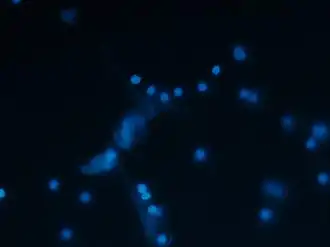

High-resolution scanning electron microscopy has shown that NETs consist of stretches of DNA and globular protein domains with diameters of 15-17 nm and 25 nm, respectively. These aggregate into larger threads with a diameter of 50 nm.[2] However, under flow conditions, NETs can form much larger structures, reaching hundreds of nanometers in length and width.[4]

Analysis by immunofluorescence corroborated that NETs contain proteins from azurophilic granules (neutrophil elastase, cathepsin G and myeloperoxidase), specific granules (lactoferrin), tertiary granules (gelatinase), and the cytoplasm; however, CD63, actin, tubulin and various other cytoplasmatic proteins are not present in NETs.[2][5]